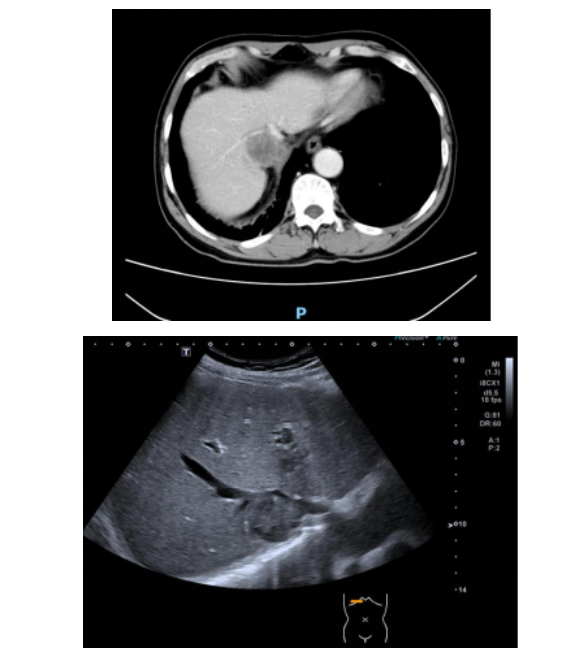

患者入住该院后,临床医师考虑到 CT 下穿刺难度大,建议其前往超声科评估是否存在超声下的安全穿刺路径。接诊后,超声科介入团队高度重视,立即对患者进行全面细致的超声影像学评估。检查发现,患者肝 S1 段占位前方有肝右静脉横亘,穿刺路径上亦有多条血管阻挡,常规穿刺路径完全行不通。经反复扫查病灶位置、大小、形态,并精准标记病灶周边血管走行与毗邻关系,团队最终锁定了唯一的安全穿刺通道。

本次穿刺由主治医师胡震主刀。在超声实时动态引导下,胡震屏息凝神、稳扎稳打,手持穿刺针在超声影像的「导航」下,沿着术前规划的精准路径缓缓推进。全程紧盯屏幕,实时调整进针角度,在错综复杂的血管缝隙中「穿针引线」。每一步推进都精准到毫米,完美避开所有高危血管,准确命中病灶无血管遮挡的边缘部分。